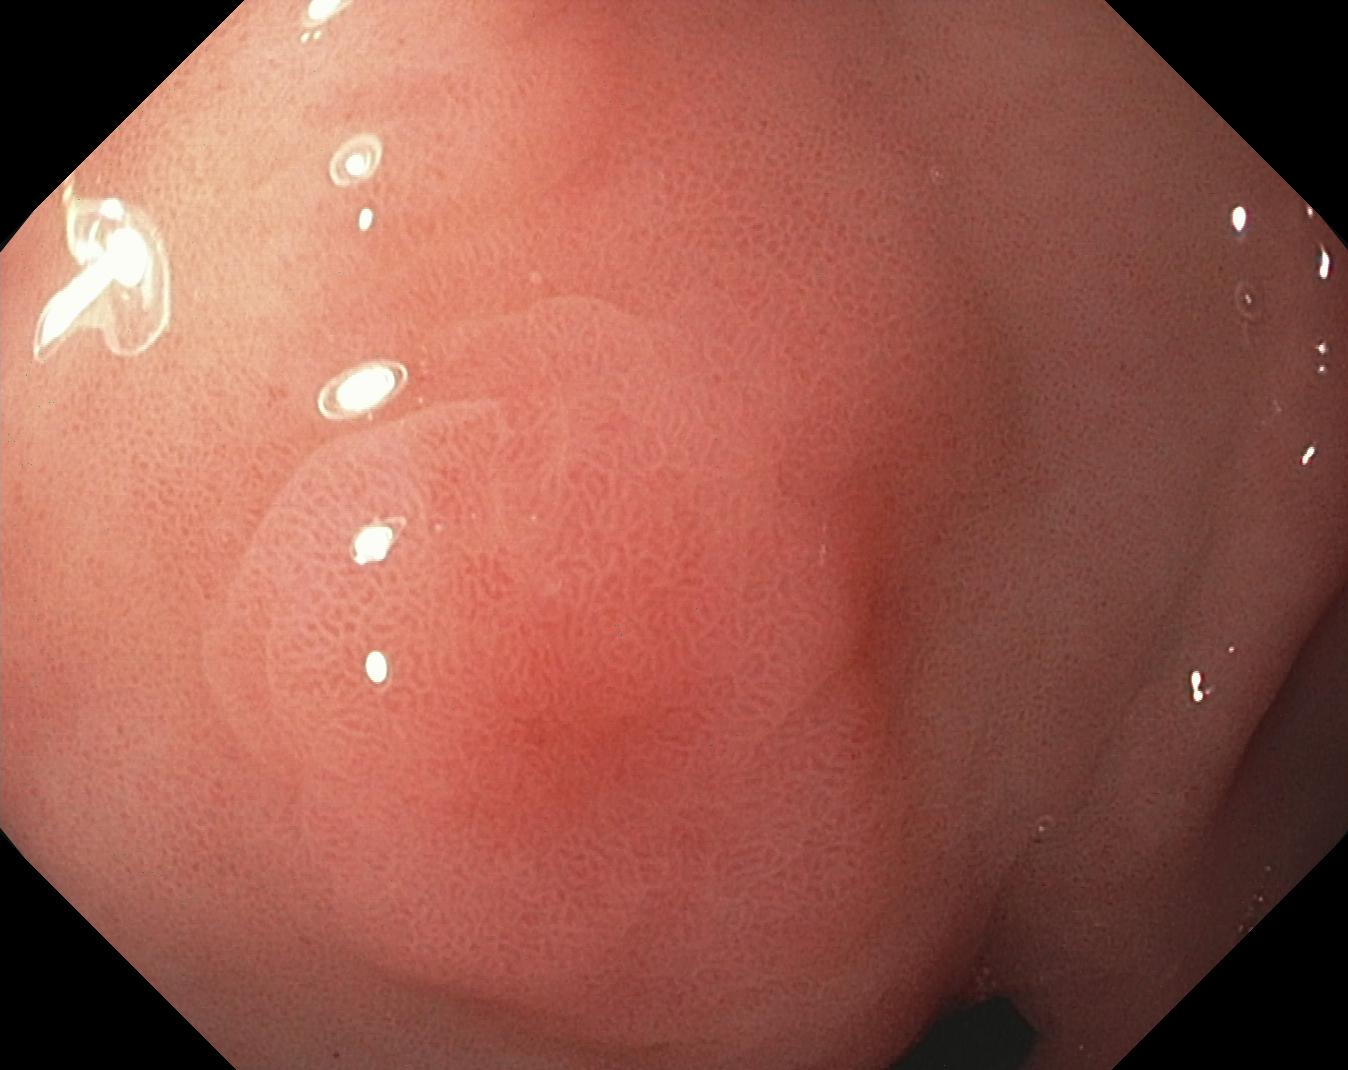

As part of the EndoCV2021 challenge (https://endocv2021.grand-challenge.org/), we were tasked with creating machine learning models that automatically segment polyps [11, 12, 13] in video frames collected from real-world endoscopies. This is a complex task as polyps come in various shapes and sizes, where some (e.g., flat lesions) are barely detectable by even the most experienced endoscopists. Figure 1 shows some of the more difficult examples taken from EndoCV’s development dataset [10] provided by the challenge organizers. The challenge presented two separate tasks, the detection generalization challenge and the segmentation generalization challenge. We participated in the segmentation generalization challenge, where we achieved the best results among 13 other competitors in both rounds. The code for the experiments presented in this paper is available on GitHub111https://github.com/vlbthambawita/divergent-nets.

Figure 4 shows some example masks predicted by our best performing model (DivergentNets) together with masks produced by the intermediate models. We see that each intermediate model learns slightly different features, making an overall more precise segmentation mask when combined. For example, the first row of Figure 4 shows the predicted masks and ground truth of a large polyp. We see that each model predicts slightly different masks for the same input and that TriUNet over-estimates the size of the polyp. After averaging the predicted masks for DivergentNets’ final output, this area is smoothed out by the predictions from the other intermediate models.

Even though DivergentNets primarily produces more accurate masks than any single model, there are cases where masks from the intermediate model better match the ground truth. We see this in row three, where DeepLabv3+ produces a more precise mask than all other intermediate models, making the averaged output less accurate.